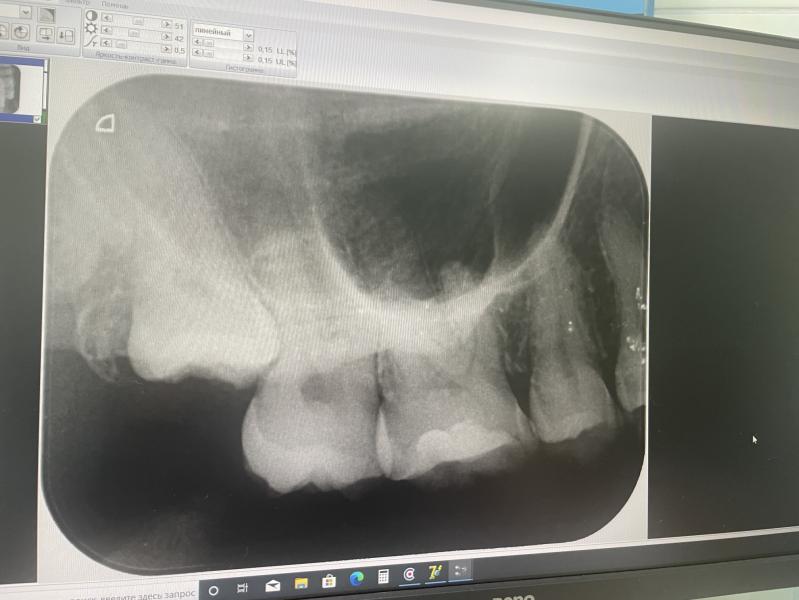

@mar_k123, ну тут видно он уже уперся и встал прям под 7

Может начать двигать зубной ряд

Это 8-ка я так понимаю ? А чего именно врач ждать собрался , он объяснил? Пока он разрушит соседний ? Найдите другого врача , просто хотя бы для второго мнения